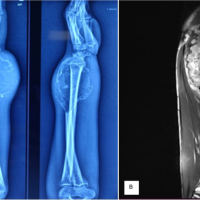

A 12-year-oldgirl presented to OPD after a fall over right elbow while playing at home with pain and limitation of movements. On examination, we observed that pain aggravates on movement and there was tenderness over head of radius and it was aggravating on supination and pronation of forearm. We have also noted mild swelling over tender extremity. Range of motion was limited and painful in supination and pronation, flexion and extension with active finger movement, and distal pulse present. There was no distal neurovascular deficit. following which X-ray was taken and she was diagnosed with displaced fracture neck of Right (JUDET TYPE IV b CLASSIFICATION as shown in Fig. 1).

Reduction was found to be unsuccessful and elbow was found to be subluxating after closed reduction. Then open reduction was attempted. About 5 cm Incision(lateral kochers approach) made over lateral aspect of elbow joint. Skin, fascia, and subcutaneous tissue incised and retracted. Intramuscular plane identified between anconeus and extensor digitorium communis. After separating these two muscles radius, head was exposed as given in (Fig. 3). Fracture site found to be completely displaced by 180° (radial articular surface facing fracture site) as given in (Fig. 4). After removing interpositioned tissue, fracture site was freshened. After correcting anatomical reduction, the 1.25 mm Kirschner wire is passed from lateral to medial (taking care to protect the posterior interosseous nerve by hyper pronation) in elbow and flexed to 90° as shown in (Fig. 5). Reduction checked under c arm found to be satisfactory in flexion and extension (Fig. 6) of elbow and supination and pronation of forearm. Radiocapitellar line found to be intact throughout the range of motion. Thorough wound wash given. Wound closed in layers and sterile dressing done and above elbow slab applied. Immediate post-operative X-ray was taken and found to be satisfactory sequential monthly follow-up X-ray was taken and k wire was removed as shown in (Fig. 7). After 3-month postoperatively, she has good functional outcome of the right elbow joint as shown in (Fig. 8).